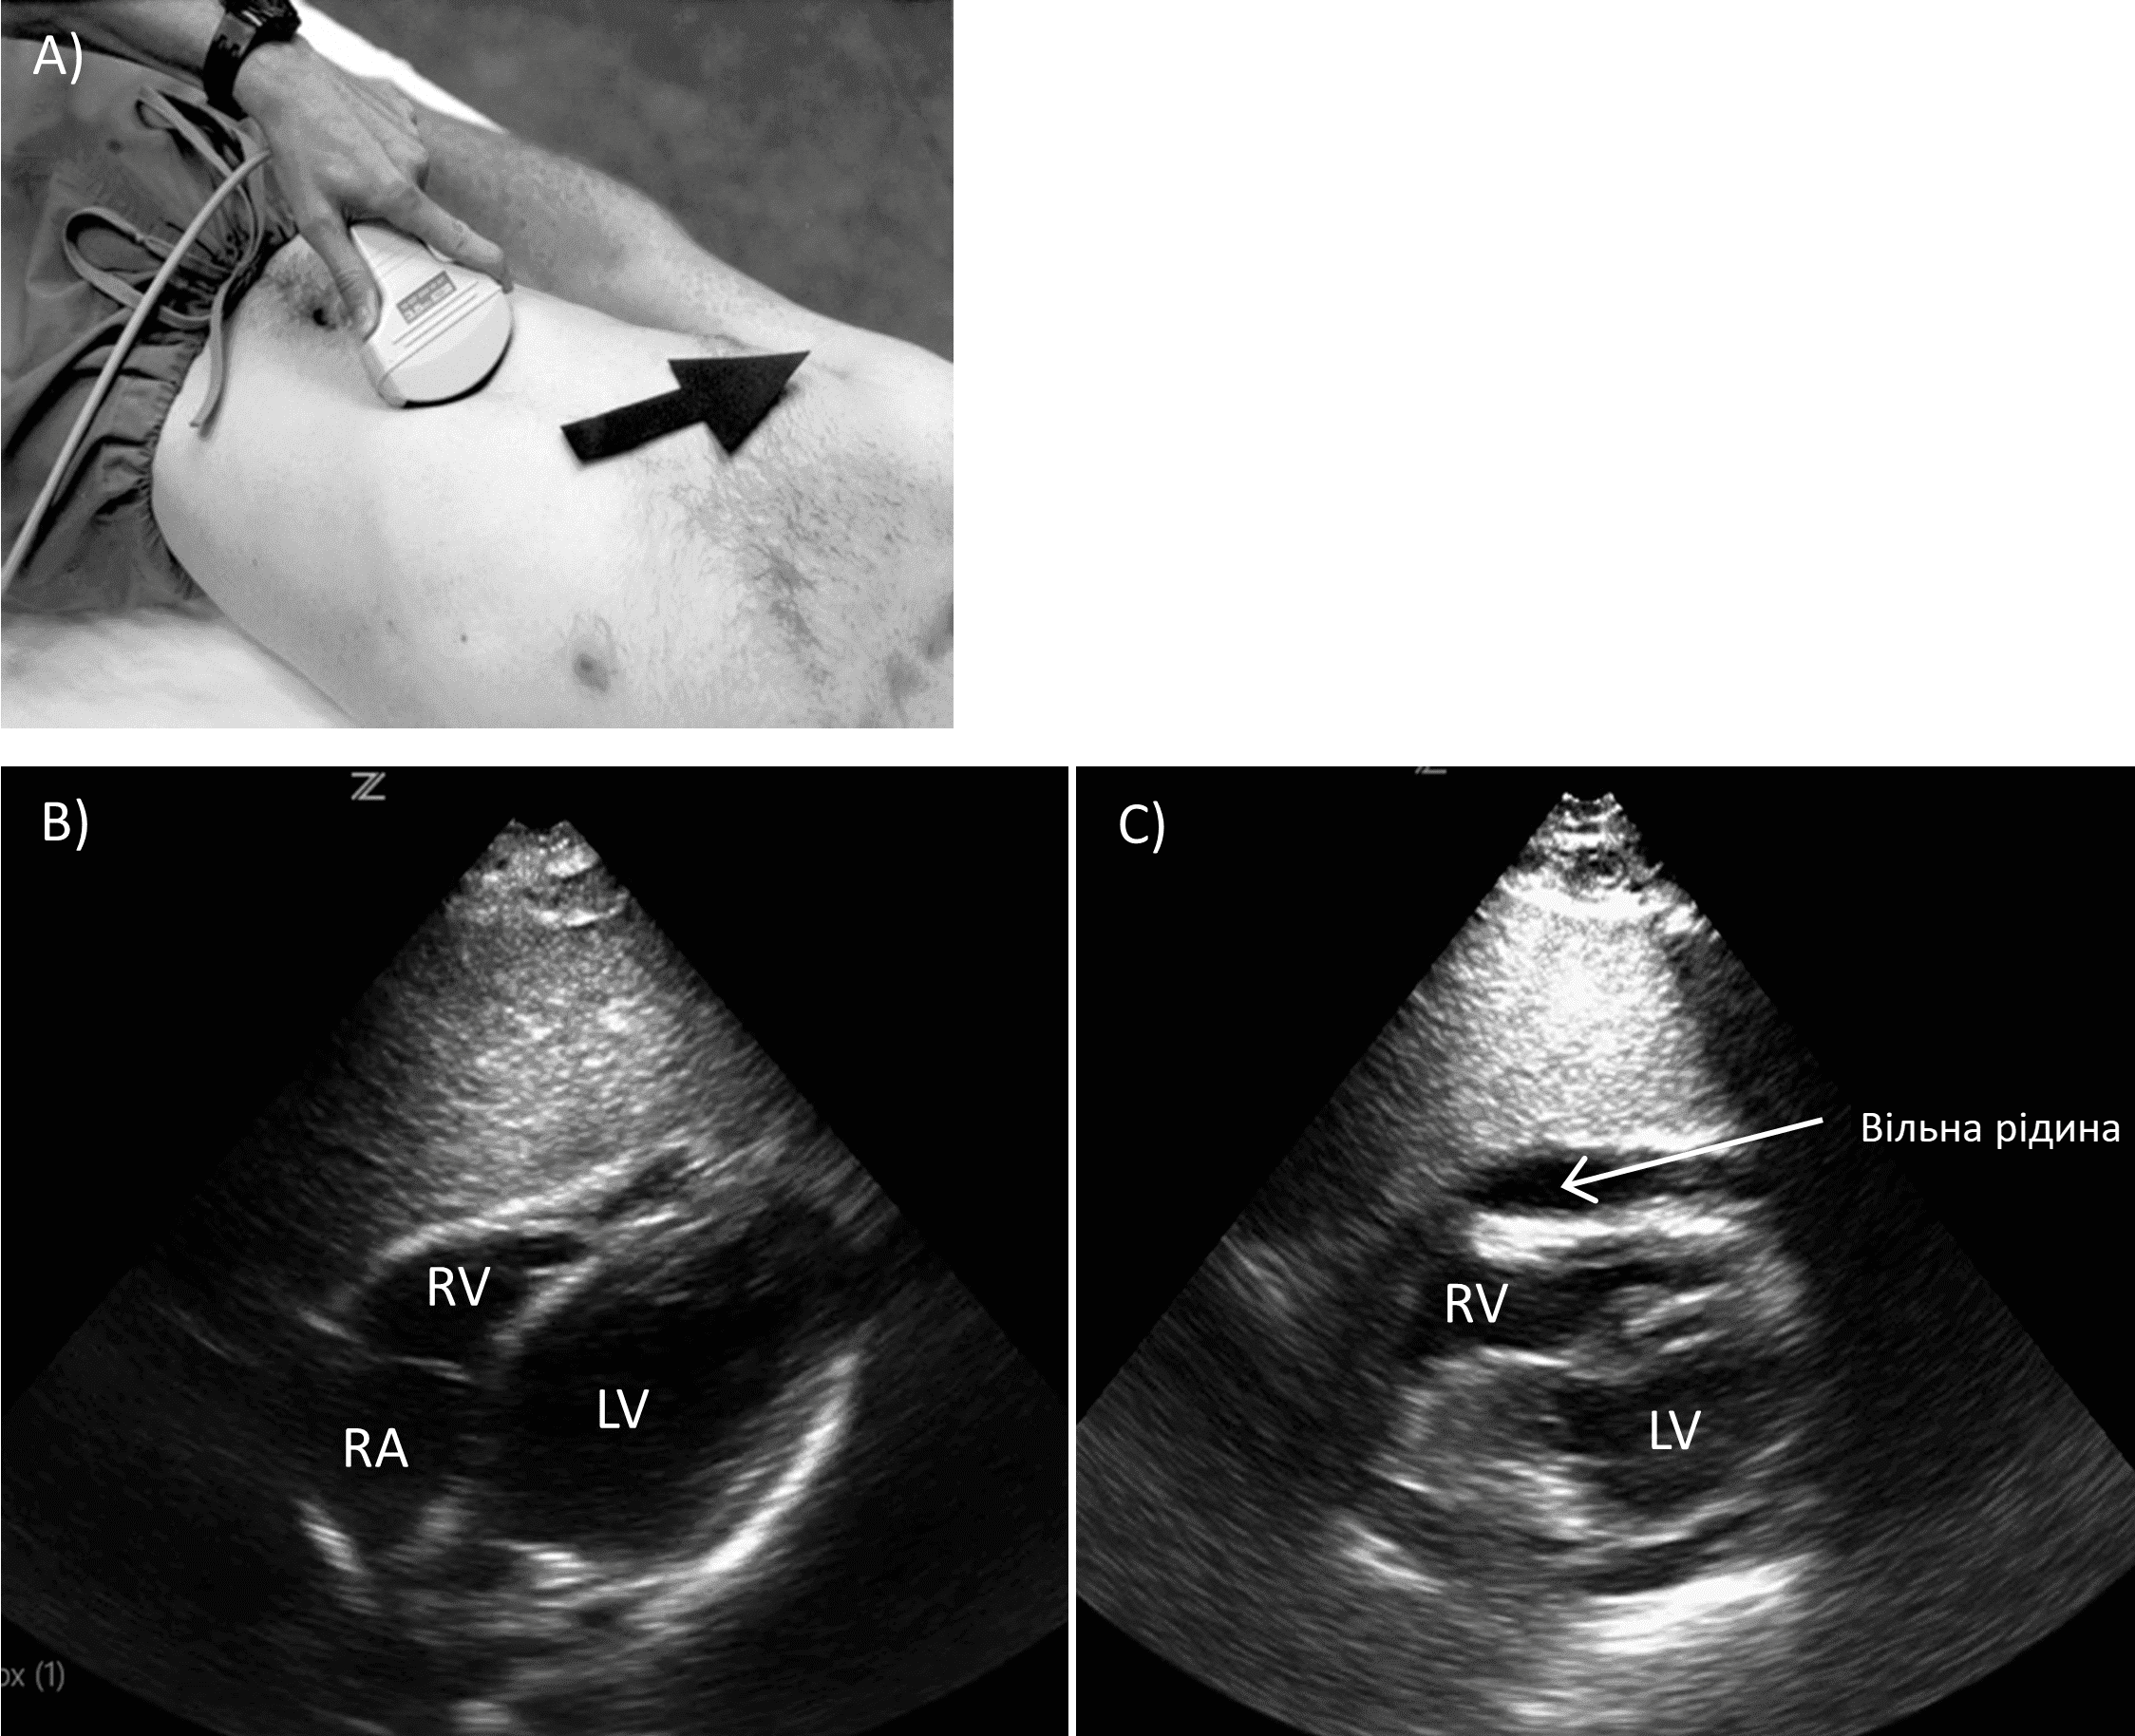

Перикард, як правило, оцінюється за допомогою субксифоідального доступу. Конвексний датчик розміщують під мечеподібним відростком груднини поперечно, маркер на датчику спрямований праворуч від пацієнта. Зонд обережно розташовують під мечоподібним виростком та скеровують догори так, щоб він майже пласко лежав уздовж живота пацієнта (Зобр. 2).

Зобр. 2. Субксифоідальний доступ.

A)

Позиціонування датчика. B) Норма. C) Перикардіальний випіт RV (правий шлуночок), RA (праве передсердя), LV (лівий шлуночок)

Як правило, це не потребує значного тиску, і за правильного виконання пацієнт не повинен відчувати значного дискомфорту під час цього маневру. Повинні візуалізуватись всі чотири камери серця. Перикардіальний випіт виглядає як анехогенна смуга. Важливо відрізнити перикардіальний випіт від перикардіальної жирової тканини, яка рухатиметься разом із серцем під час його скорочення. Випіт не рухається. Пацієнтам із ознаками тампонади може знадобитися негайне хірургічне втручання, включаючи торакотомію.